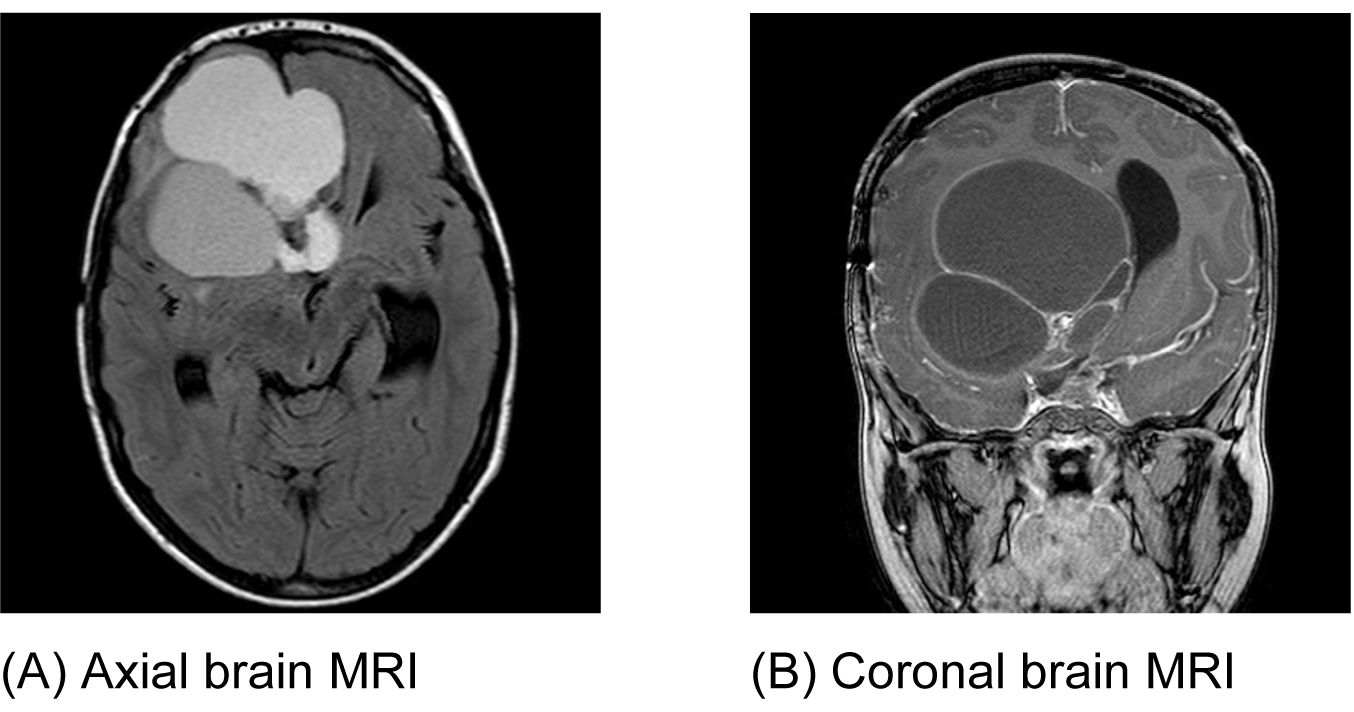

An eight-year-old boy was referred by an ophthalmologist to the Pediatric Oncology Center (Cape Town) in 2004. He presented with features of hypopituitarism and bilateral optic atrophy. His imaging studies showed a ring enhancing lesion with solid and cystic components arising from the suprasellar area and compressing the third ventricle (V3) with associated hydrocephalus. A subtotal resection and left subdural shunt was performed at that time, and a histological diagnosis of CP was made hormonal replacement was initiated. A year later following his first recurrence the patient was treated with repeat debulking resection and at this time an Ommaya reservoir was placed. Further subtotal resection to the growing lesion, followed by adjuvant radiotherapy (54 Gy) was done the following year after he had turned three years old. At this point, multi-modality treatment allowed for disease stability for another three years, when evidence of disease progression was again noted. This prompted surgical re-intervention and a debulking procedure was again performed. In June 2011, at the age of eight, radiological evidence of tumor recurrence was again noted (Figure 1A-B) and after multi-disciplinary discussion, treatment with intracystic IFNa-2b was proposed as an alternative method of gaining local control and thereby controlling disease progression. A pre-treatment leakage test was done via the Ommaya reservoir and this showed extensive leakage around the catheter into the right ventricle. (Figure 2) There was thus concern over the potential for leakage during IFNa-2b treatment and the clinical implications of this were researched. The treating multi-disciplinary team enlisted further advice from international colleagues regarding the safety of IFNa-2b administration in such a situation. Following this advice and the information obtained through documented research, a decision was made to proceed with the therapy as intra-ventricular spillage of IFNa was considered to be innocuous. The first cycle was given intratumorally at a dose of 3,000,000 international units. This dose was then administered three times a week for a total of four weeks. During these treatment sessions, the patient exhibited severe lethargy. Two weeks after completing the full planned course he presented with confusion, urinary incontinence and was found to have hypernatremia and hyperthyroidism. Magnetic resonance imaging (MRI) of the brain, at that point revealed significant brain atrophy, striking volume loss with no significant change in the tumor size and an increase in hydrocephalus. (Figure 3A-B) The patient was admitted and his condition stabilized following appropriate management. His hormonal replacement medications were adjusted and a shunt was inserted to drain the re-accumulating hydrocephalus. He was seen again in the combined Pediatric Neuro-Oncology clinic a month later, and was clinically stable. It was thus decided to forgo further IFNa-2b therapy due to concern about further complications. He will thus be followed at regular intervals for symptom control and monitoring of his endocrine functions. | ||||||